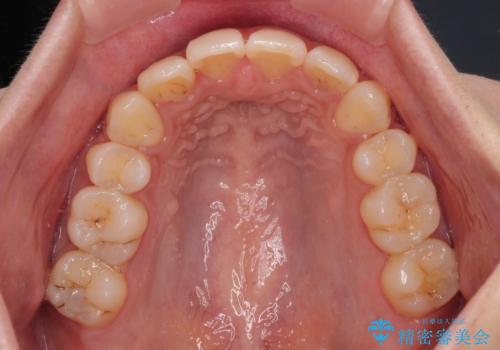

上下の前歯が接触する仕上がりとなったので、横顔の印象が大幅に改善されました。

アンカースクリューと補助装置を使用して上顎大臼歯を遠心移動させることで咬み合わせを改善し、更には口元の突出感を改善するために上下左右の小臼歯4本を抜歯し、ワイヤー装置によりデコボコを解消しながら口元の突出感も改善していくこととしました。